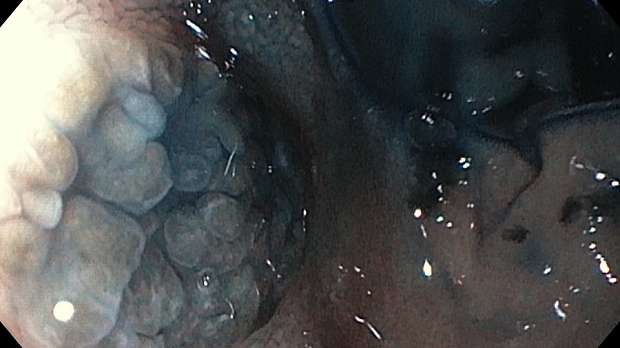

Эзофагогастродуоденоскопия диагностическая

Olympus EVIS EXERA III GIF- H185

12-кишка: Просвет луковицы двенадцатиперстной кишки обычный, содержит небольшое количество желчи, перистальтика активная , слизистая оболочка розового цвета, ворсинки сохранены. Так же прослеживаются пигментированные образования от 2мм до 8мм. серо-синюшного оттенка. Постбульбарном отделе множественные пигментые образования до 10мм, единичные кратообразные пигментные образования до 15мм, глубиной до 5мм., дно покрыто серым фибрином. Биопсия 2-а кусочка.

Заключение: ГПОД. Грыжевая гастропатия. Эрозивная гастропатия антрального отдела желудка. MTS Меланома ЛДПК, залуковичного отдела. Биопсия.